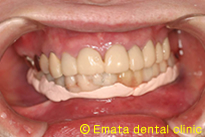

After

手術開始から約4時間後、その日のうちに歯が入りました。

これで、食事がしやすくなりますね。但し、2ヶ月間は硬いものには注意して下さい。